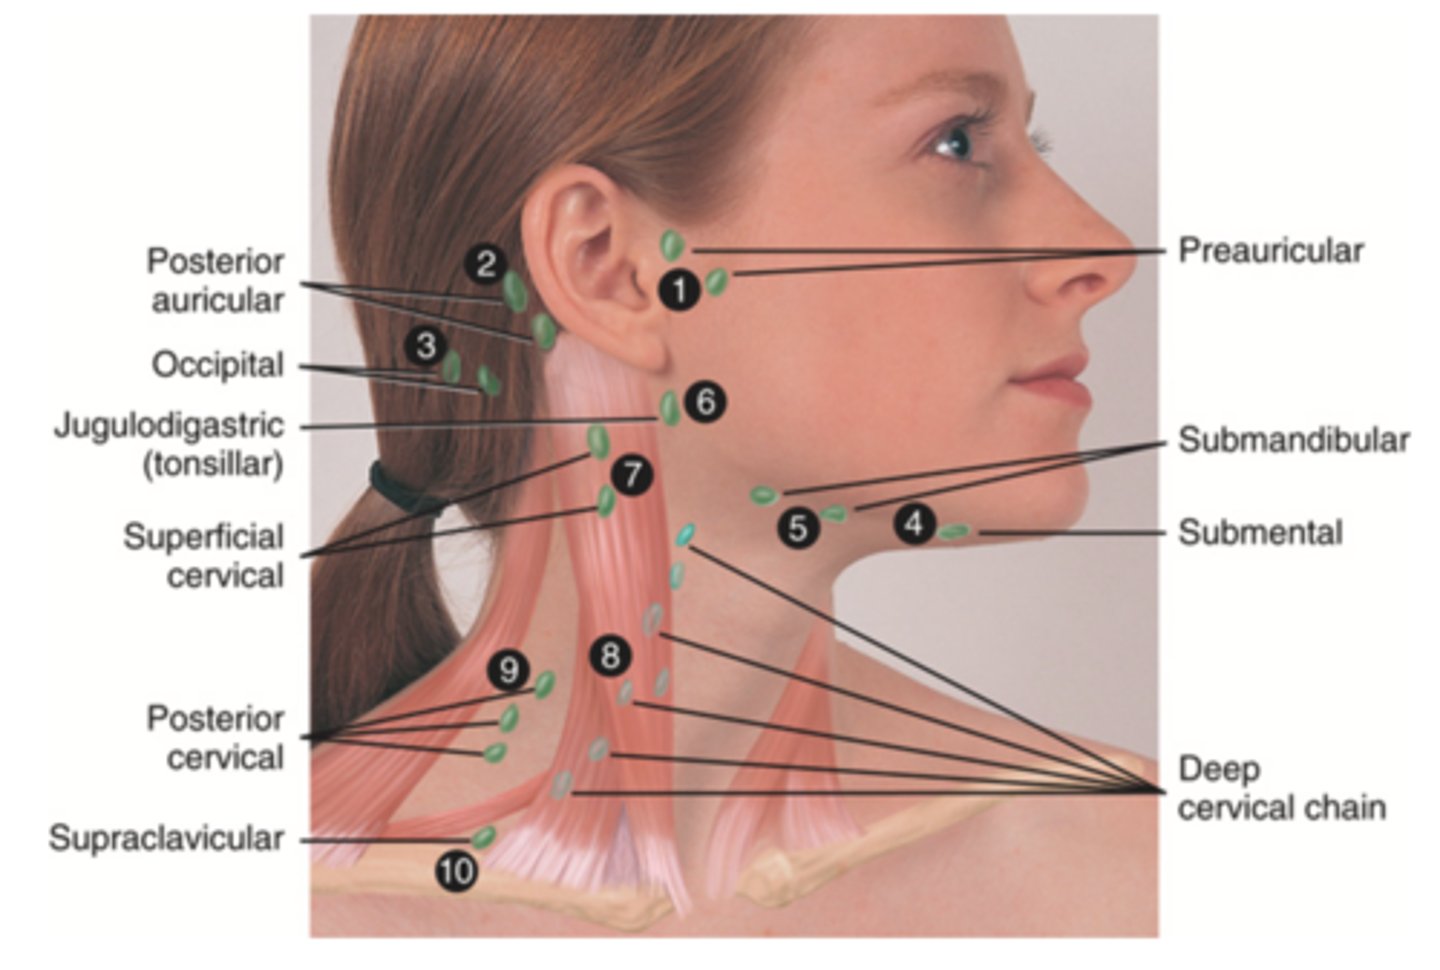

Major Lymph Nodes in the Neck (FUN!)

- Preauricular

- Posterior auricular

- Occipital

- Submental

- Submandibular

- Jugulodigastric (tonsil)

- Superficial cervical

- Deep cervical chain

- Posterior cervical

- Supraclavicular

(Party People Often Sell Sardines Just So Dogs Pee Silver)

Preauricular Lymph Node

Lymph node in front of the ear (1)

Posterior Auricular Lymph Node

Lymph node behind the ear (2)

Occipital Lymph Node

Lymph node at the base of skull (3)

Submental Lymph Node

Lymph node under the chin (4)

Submandibular Lymph Node

Lymph node along base of mandible (5)

Jugulodigastric (Tonsil) Lymph Node

Lymph node under the angle of the mandible (6)

Superficial Cervical Lymph Node

Lymph node overlying the sternomastoid muscle (7); can feel enlarged even when there are no problems

Deep Cervical Chain Lymph Node

Lymph node located on the posterior triangle of the neck (8)

Posterior Cervical Lymph Node

Lymph node in the posterior triangle along the edge of the trapezius muscle (9)

Supraclavicular Lymph Node

Lymph node just above and behind the clavicle, at the sternomastoid muscle (10)